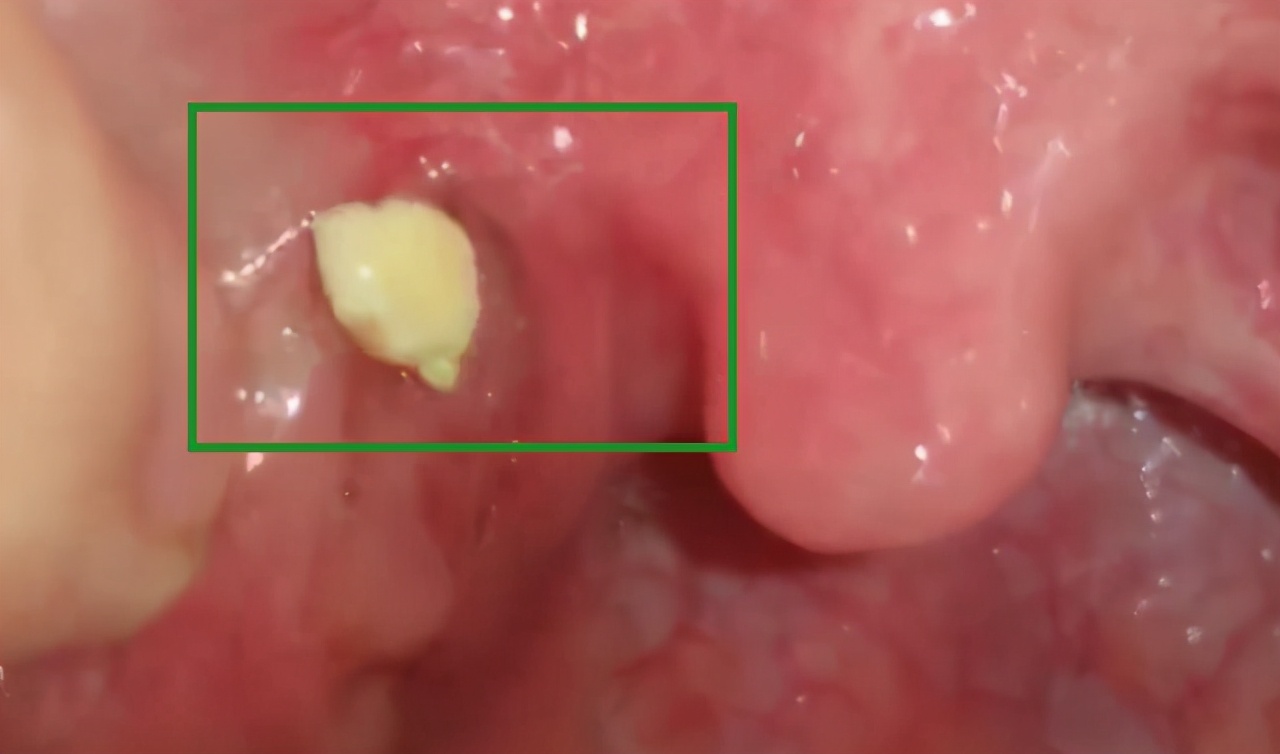

我按照亲戚教的办法,对着镜子嘴巴张大发“啊”的声音,果然能看到扁桃体处周围还有几粒白色的小颗粒,说明还有结石在那,闻了闻咳出来的结石,散发着一股臭臭的鸡蛋味。最后在众人的集思广益下,帮我把剩下的结石抠了出来,我感觉我再也没脸见人了,实在是尴尬到了极点。

医生劝告所有人,扁桃腺结是比较隐秘的,需要自己多观察才能及时发现的,一般呈现淡黄、黄绿、米,而且会发出类似臭鸡蛋味的气体,这也是很多人口臭的根本原因!如果你有严重口臭,或者时常觉得喉咙卡卡的不舒服,可以自测一下自己有没有扁桃体结石~

第3步:嘴巴张大发啊的声,对着镜子照能看到白色小颗粒就说明有结石

首先要嘴巴张大成“啊”,对着镜子慢慢找到结石所在的位置,用几根棉签挤压结石周围,然后轻轻弄掉。如果觉得自己不专业或手抖的,建议到医院检查取出,避免对扁桃体造成损伤。